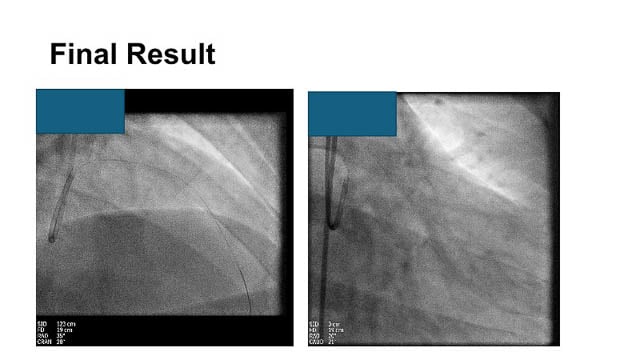

PCI for complex bifurcation disease - LIVE Case

A 60-year-old male patient presented with an inferior STEMI one month ago, which was treated with RCA and LCx PCI. He was referred for LAD/diagonal PCI. The LV function was reduced (EF 45 %). The team performed a DK crush PCI, guided by IVUS.

LIVE Educational Case...